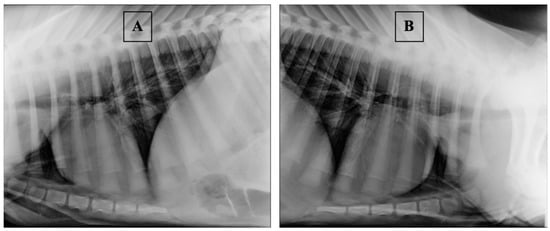

- Farrow, C.S. Bovine pneumonia. Its radiographic appearance. Vet. Clin. N. Am. Food Anim. Pract. 1999, 15, 301–358. [Google Scholar] [CrossRef]

- Fowler, J.; Stieger-Vanegas, S.M.; Vanegas, J.A.; Bobe, G.; Poulsen, K.P. Comparison of Thoracic Radiography and Computed Tomography in Calves with Naturally Occurring Respiratory Disease. Front. Vet. Sci. 2017, 4, 101. [Google Scholar] [CrossRef] [PubMed]